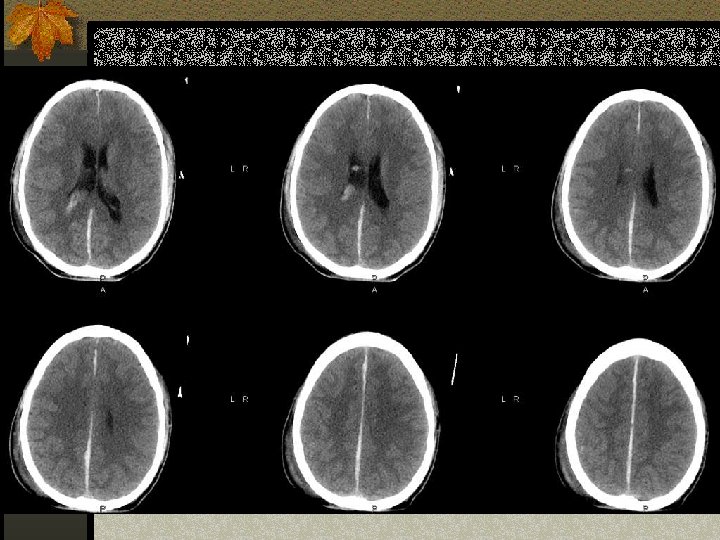

HERNIASI OTAK

HERNIASI SUBFALCIAL n Subfalcial: pergeseran girus cingulatum di bawah tepi bebas falx bersama dengan arteri pericallosal. n Dapat menimbulkan infark arteri serebri anterior

HERNIASI UNCAL n Pergeseran medial lobus temporal melalui n n n tentorial notch Pergeseran midbrain Effacement of the suprasellar cistern Pergeseran pedunculus cerebri kontralateral terhadap tentorium Pelebaran ipsilateral cerebello pontine angle Penekanan arteri serebri posterior

DOWNWARD HERNIATION n Caudal displacement of the thalamus and midbrain n Effacement of the perimensencephalic cistern and 4 th ventricle. n Dapat menyebabkan palsi N. III dan merusak pembuluh darah pons yang bisa menyebabkan perdarahan batang otak

UPWARD HERNIATION n Akibat massa fossa yang menyebabkan pergeseran vermis ke superior displacement of the vermis melalui tentorial incisura n Penekanan ventrikel IV dan effacement of the quadrigeminal plate cistern. n Kompresi arteri cerebellar superior

TONSILLAR HERNIATION n Pergeseran tonsil serebelli ke inferior melalui foramen magnum n Dapat menyebabkan infark arteri serebelli posterior